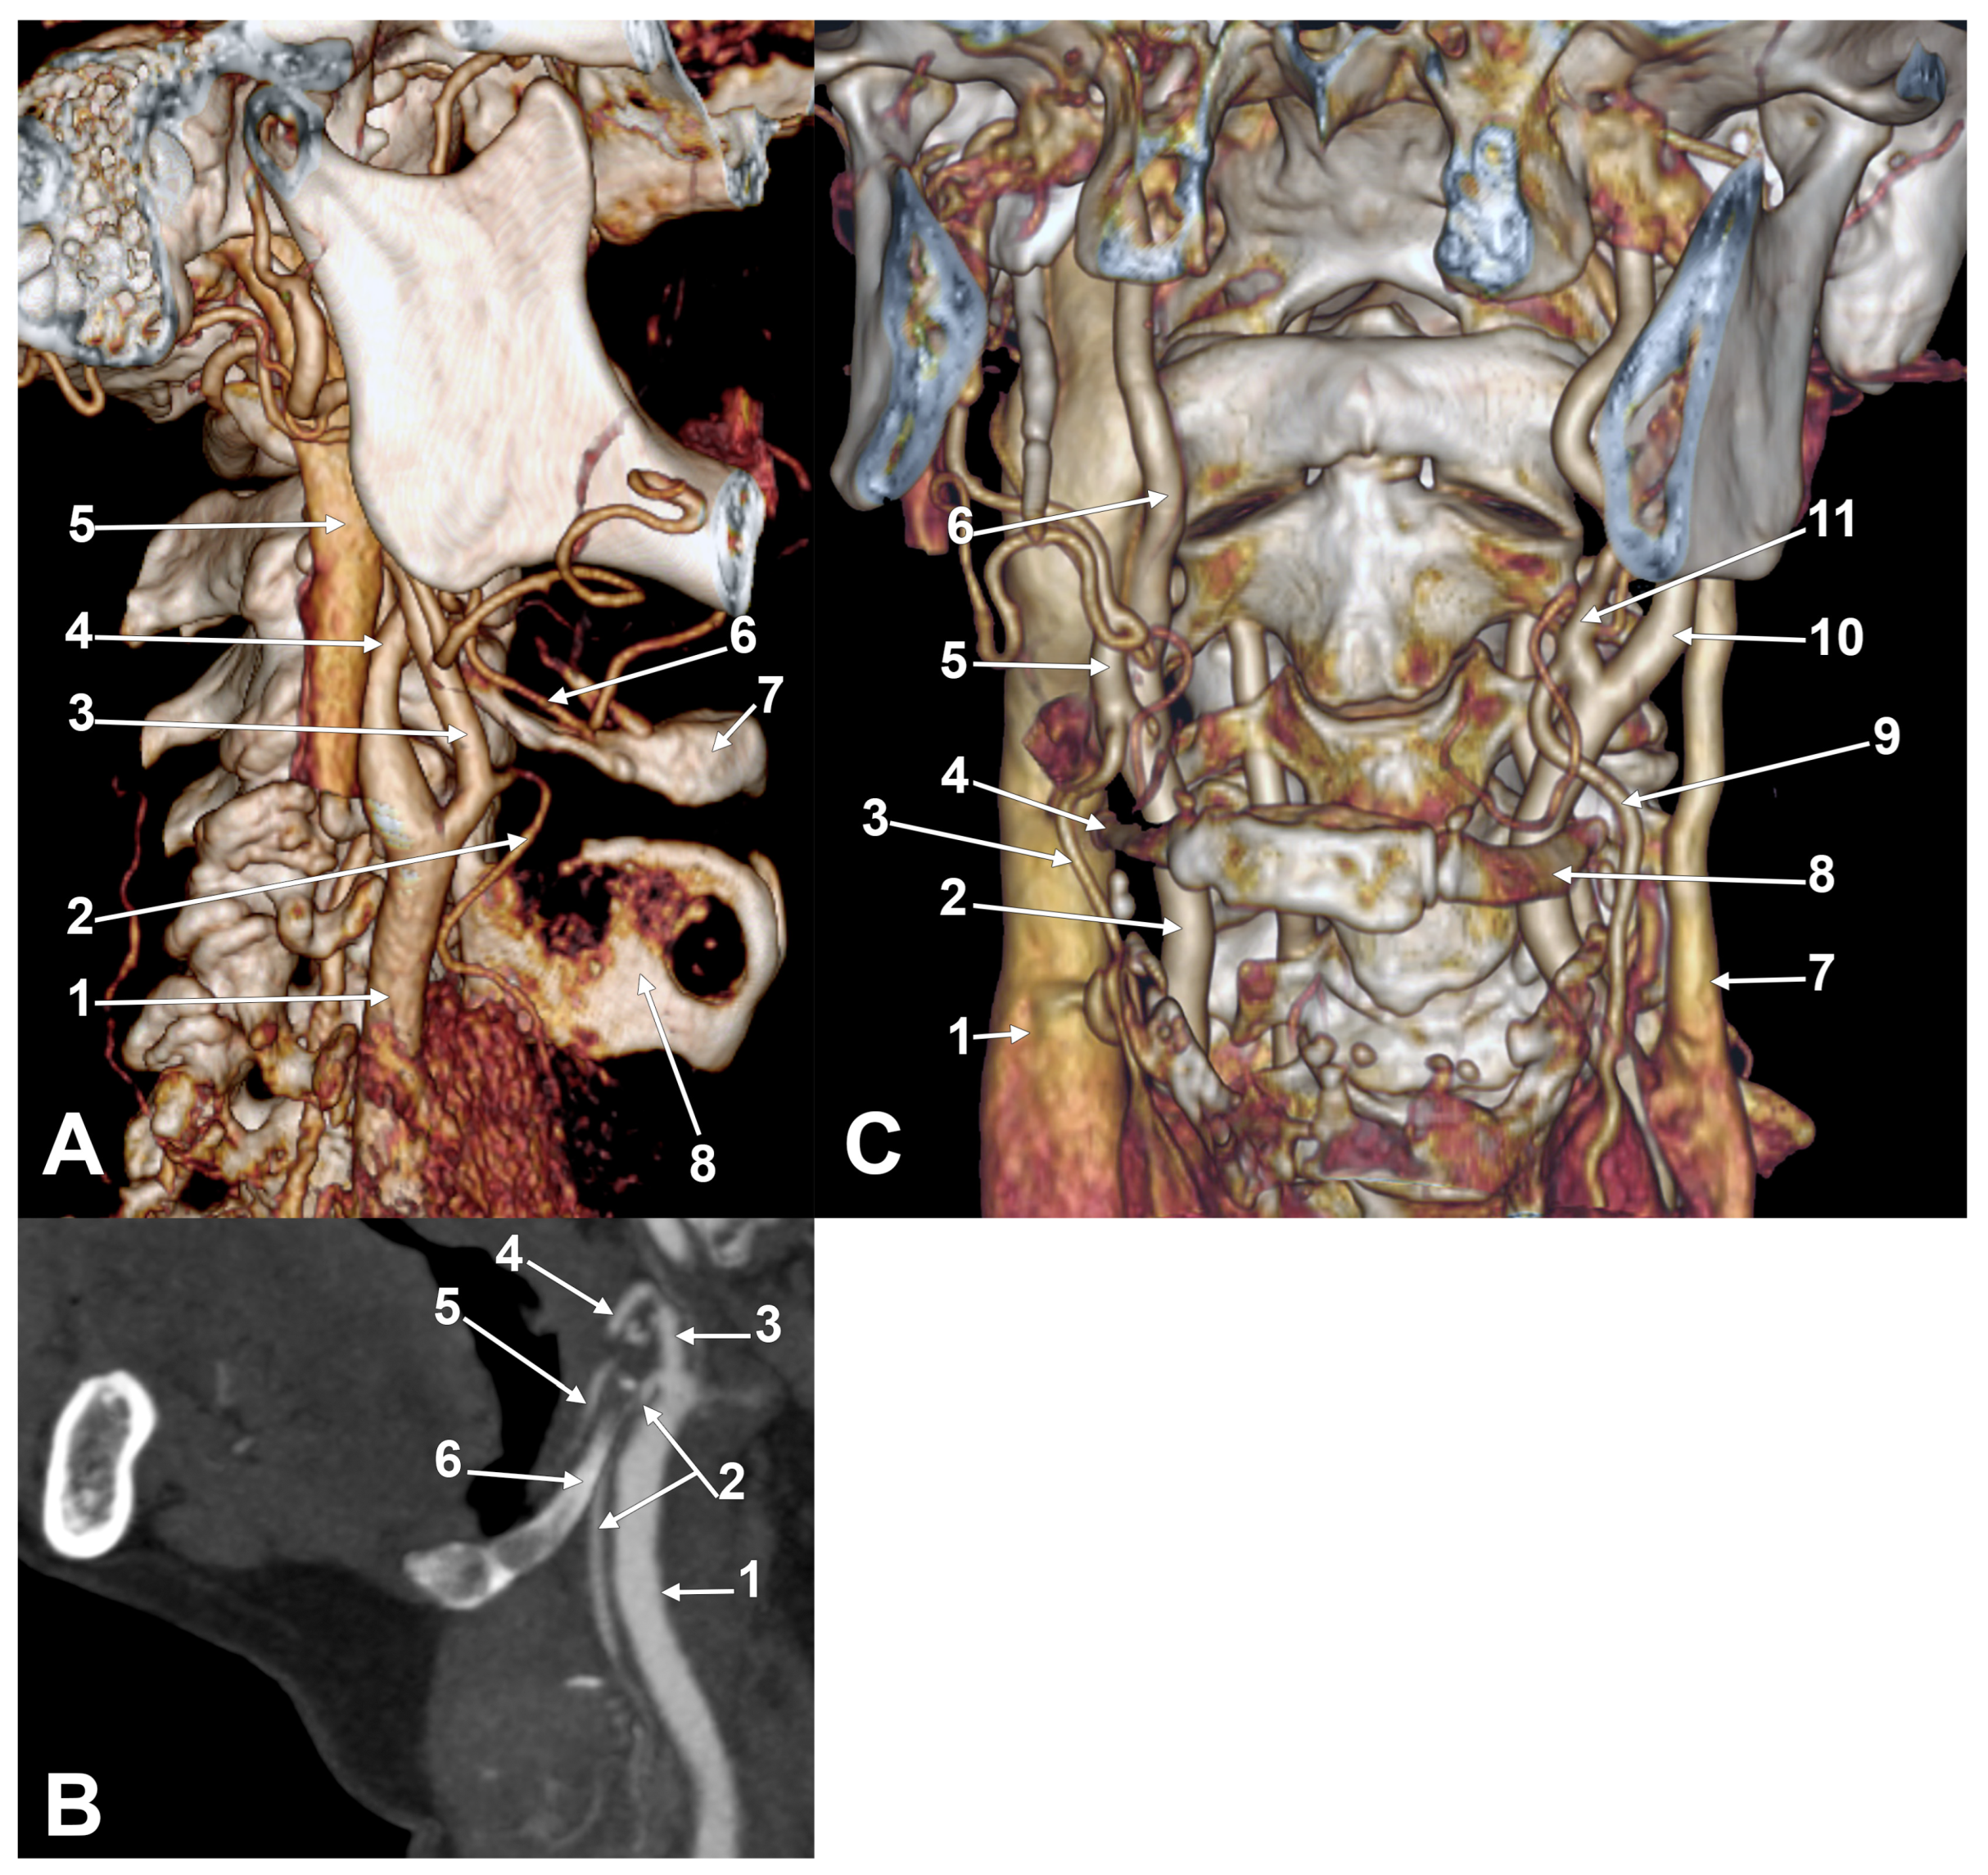

Appendix A.2. Supplemental Figures